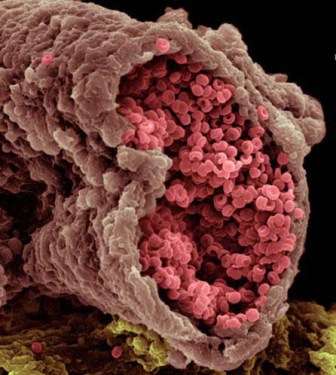

سرخرگ

گلبولهای قرمز

سلول های خونی